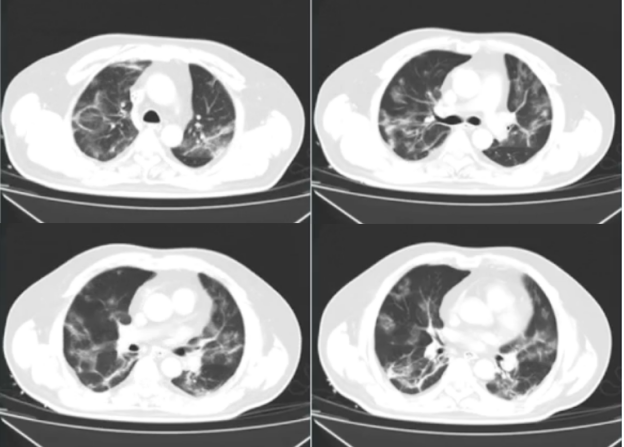

拔管后胸部CT可见斑片样渗出明显改善(图3),PaO2升高,氧合改善。

图3  患者拔管后复查胸部CT(4月13日)